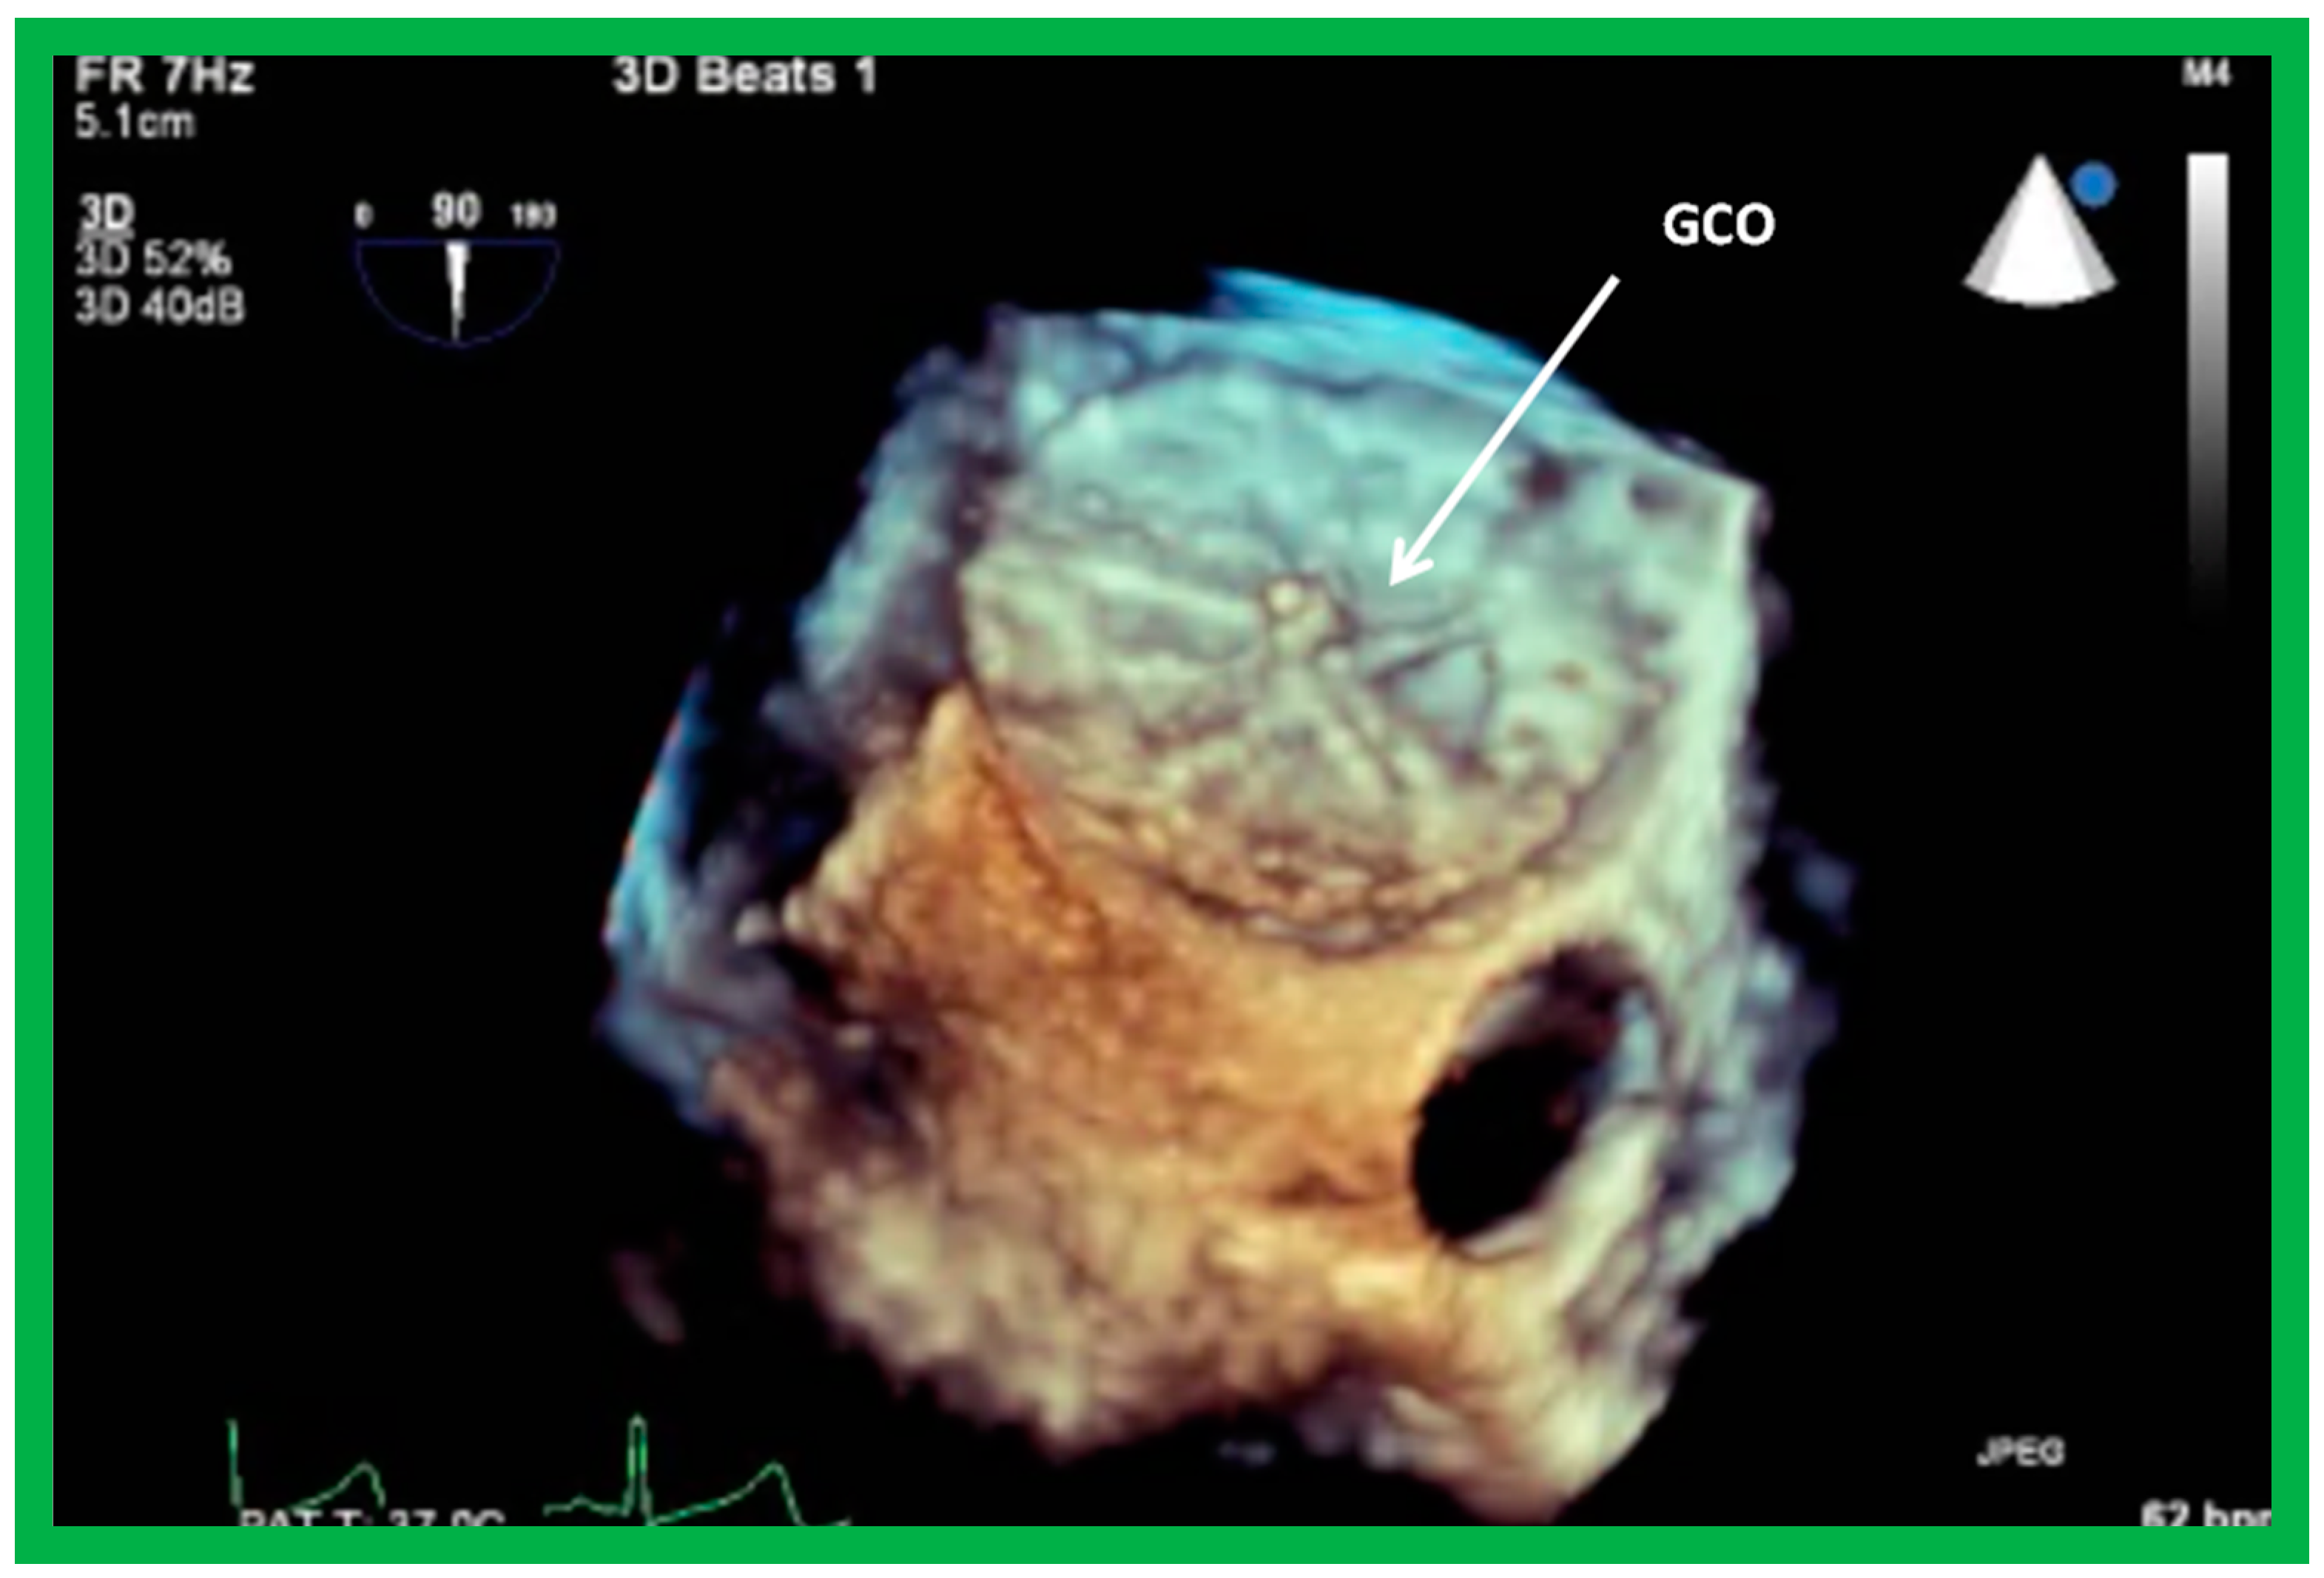

8.4. GORE® CARDIOFORMASD Occluder (GCO)

- Gillespie, M.J.; Javois, A.J.; Moore, P.; Forbes, T.; Paolillo, J.A.; for the GSO Investigator Group. Use of the GORE® CARDIOFORM Septal Occluder for percutaneous closure of secundum atrial septal defects: Results of the multicenter U.S. IDE trial. Catheter. Cardiovasc. Interv. 2020, 95, 1296–1304. [Google Scholar] [CrossRef]